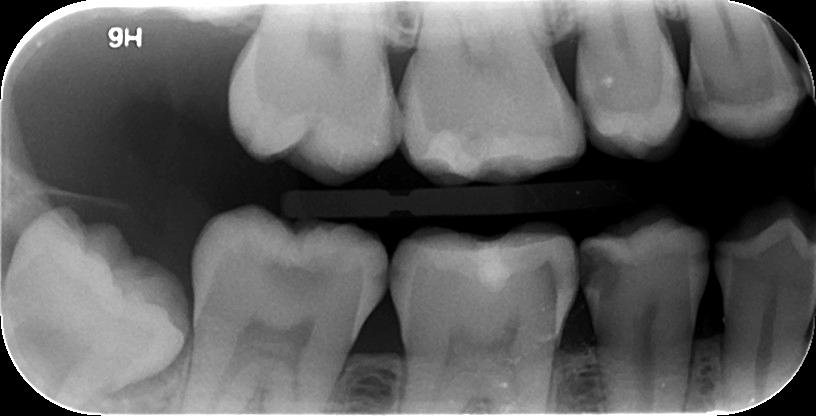

3. ΟΠΙΣΘΟΜΥΛΙΚΗ ΑΚΤΙΝΟΓΡΑΦΙΑ

Με την οπισθομυλική ακτινογραφία επιτυγχάνεται η ταυτόχρονη απεικόνιση των μυλών των άνω και κάτω οπισθίων δοντιών ενός ημιμορίου (μιας πλευράς) με μία λήψη. Λαμβάνεται με την τοποθέτηση του ακτινογραφικού πλακιδίου εσωτερικά των δοντιών (προς την πλευρά της γλώσσας και του ουρανίσκου) και παράλληλα με αυτά. Χρησιμοποιείται ειδικός συγκρατητήρας οπισθομυλικών, τον οποίο δαγκώνει ο εξεταζόμενος.

Χρησιμοποιείται για την ανίχνευση τερηδόνων στις μύλες των δοντιών, κυρίως στις όμορες επιφάνειές τους (γειτνιάζουσες επιφάνειες δοντιών).

Η λήψη της είναι γρήγορη (διαρκεί λίγα δευτερόλεπτα) και ανώδυνη.